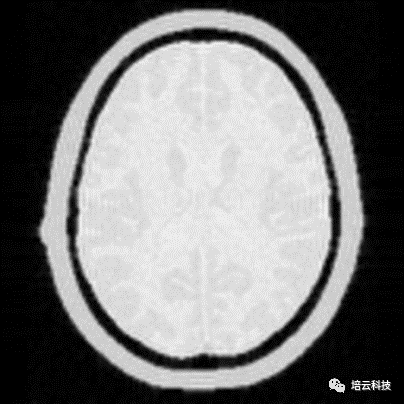

T1权重像上,T1越短的组织越亮,T1越长的组织越暗。脂肪具有短T1,水具有长T1,所以在T1权重像上,脂肪高亮而水体呈现出类似背景的暗黑。T1权重越大,图像信噪比越低。T2权重像上,T2越短的组织越暗,T2越长的组织越亮。脂肪具有中等T2,水具有长T2,所以在T2权重像上,脂肪灰暗而水体高亮。T2权重越大,图像信噪比越低。Pd权重像上,组织的亮度由组织质子密度决定。脂肪和水的质子密度相差不大,很多软组织比如白质和灰质的质子密度和水也差不多。所以质子密度像上,组织的亮度差异很小,但Pd像具有极高的信噪比。综上可知,图像对比度和信噪比也是矛盾的,与信噪比作为矛盾统一体的还有空间分辨率。图10分别是T1WI、T2WI和超重T2权重的水成像以及PdWI的仿真图像效果。水成像上,除了水体是亮的,其余所有组织都是暗的。

图10 T1WI、T2WI和超重T2权重的水成像以及PdWI的仿真图像效果